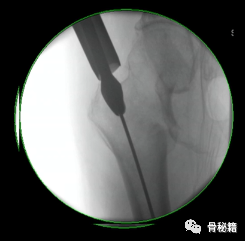

2、股骨干部复位,工具比不可少,主要是金手指

复位时注意要用一些肌松和适当的牵引

很多时候金手指不太听话这个时候可以试试顺时针和逆时针旋转

3、保持复位,我们知道在扩髓时保持复位非常重要,可以用一些辅助器械来进行辅助保持复位。

对于B型骨折的蝶形骨块如果不保持复位可能扩髓之后会离的很远影响骨折愈合

对于A1.3型骨折,单纯牵引很难复位通常需要借助骨钩来复位,主要是由于小粗隆完整受到肌肉的牵拉而移位

可以在偏前方植入一枚克氏针临时固定来进行复位辅助